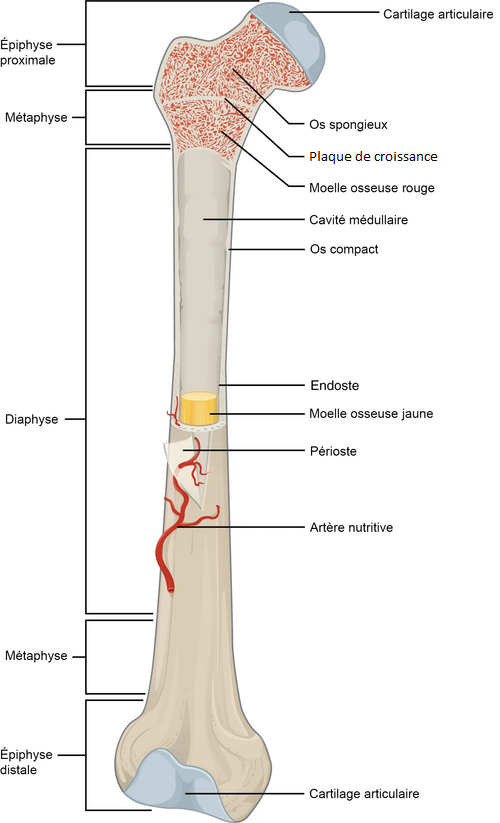

Cette structure de base – qui s’organise en lamelles – est commune à tous les tissus osseux de l’organisme, mais son agencement varie au sein et entre les différents types d’os : ainsi, chez l’adulte, le tissu osseux peut être compact ou spongieux. Le tissu osseux compact est composé de nombreuses lamelles collées les unes aux autres et ne comporte que très peu de cavités de faible volume, dans lesquelles sont présents des vaisseaux sanguins et des nerfs ; Le tissu osseux spongieux est composé de lamelles moins nombreuses mais organisées en travées, ce qui forme des cavités volumineuses au sein du tissu contenant des vaisseaux sanguins et de la moelle osseuse hématopoïétique.

Toutes les cavités internes de l’os sont tapissées d’une mince couche de tissu conjonctif cellulaire appelé endoste. La face externe de l’os, quant à elle, est recouverte par le périoste, composé d’un couche externe fibreuse et d’une couche interne cellulaire.

- Les os courts : (exemples : vertèbres, os du carpe, os du tarse…) ils sont composé d’os spongieux entouré d’une mince couche d’os compact appelée corticale ;

- Les os plats : (exemples : côtes, scapula, os du crâne, sternum…) ils sont formés de deux lames d’os compact (corticales) entourant une couche d’épaisseur moyenne d’os spongieux appelée diploë ;

- Les os longs : (exemples : fémur, tibia, humérus…) ils sont formés de trois structures :

- Les épiphyses, situées aux deux extrémités de l’os, sont constituées d’os spongieux ;

- La diaphyse, située en région centrale de l’os, est un cylindre d’os compact ou os cortical entourant une cavité centrale appelée cavité médullaire, contenant de la moelle osseuse jaune (adipeuse) ;

- Les métaphyses, situées entre les épiphyses et la diaphyse, sont constituées d’os spongieux. Pendant la croissance, elles contiennent une mince couche de cartilage à leur jonction avec les épiphyses, appelées plaques de croissance, au niveau desquelles s’effectue la croissance en longueur de l’os.